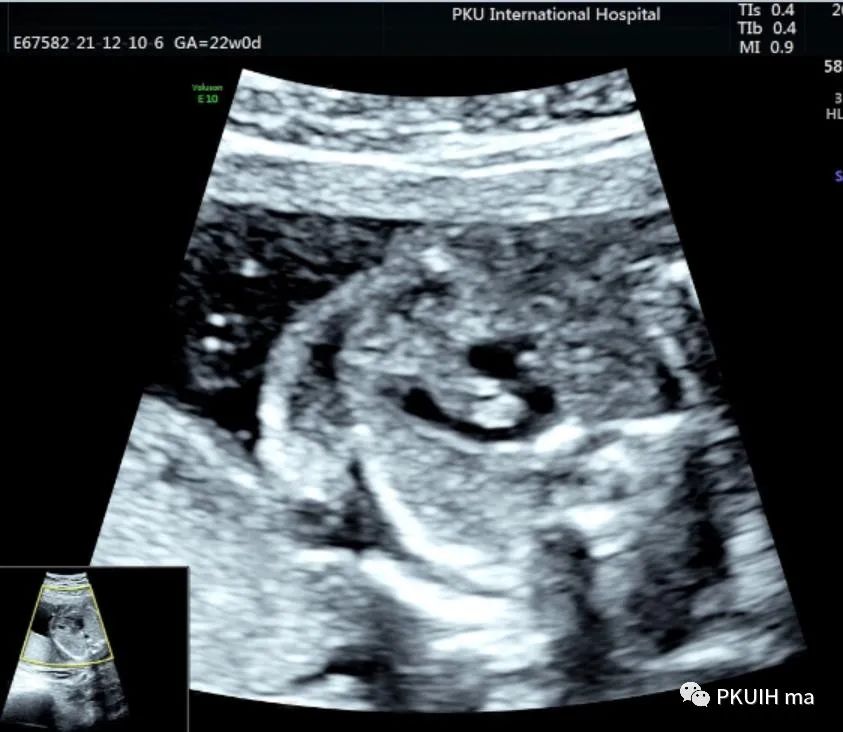

锁骨下动脉观察一般在主动脉弓水平横切面观察,显示左右锁骨下动脉像弓箭样向左右肩部走形。对于迷走的锁骨下动脉观察需要在三血管气管切面和主动脉冠状切面观察。右锁骨下动脉迷走在三血管气管切面可见一血管于主动脉弓降部发出自脊柱前方气管后方向右肩走行,在主动脉冠状切面显示主动脉弓降部见一血管迂曲向右肩部走行,频谱显示为动脉频谱。右锁骨下动脉迷走在三血管气管切面要和左无名静脉鉴别,左无名静脉汇入上腔静脉,频谱为静脉频谱,同时右锁骨下动脉也要和走形于气管后方汇入上腔静脉的奇静脉相鉴别,血流频谱有助于两者鉴别。

脊柱前方一红色血管为迷走的右锁骨下动脉,频谱为动脉频谱